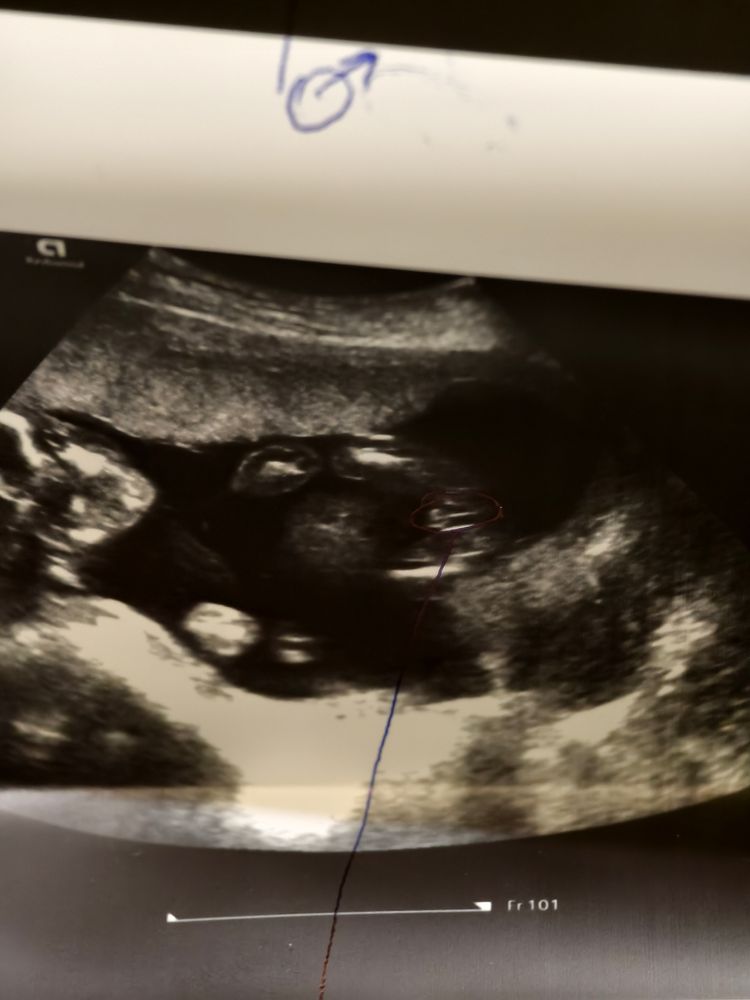

Пол малыша)

Пол малышаСегодня были на узи. Врач сказал, что признаков больше мужских) Но нужно будет все равно для подтверждения, сделать узи попозже, тк яички в мошонке еще не визуализируется. У кого есть узи мальчиков, скинете в комментарии?) интересно сравнить)

На мальчика похоже ❤️